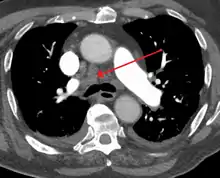

CT Thorax (axial, Mediastinal window)